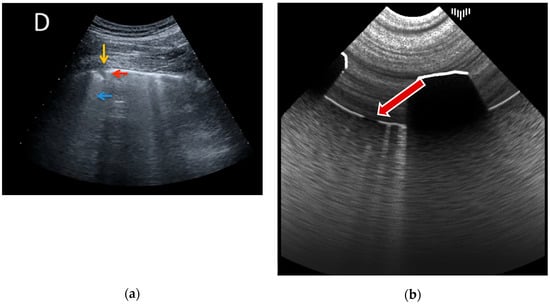

A-lines are horizontal, parallel lines seen in normal lung tissue and are created by the multiple reflections of ultrasound waves between the pleural line and the transducer. This is achieved during the ray marching step without a time-consuming ray generation: the input frame buffer, which stores the image of the first render pass, is repeatedly sampled relative to the distance of a pleural line to the transducer. The results can be seen in Figure 3.

Figure 3. A-lines example: (a) real examination; (b) the LUS simulation.